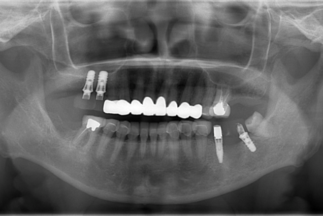

- Before

| 治療内容 | 上顎2本、下顎2本のインプラント治療による咬合再構成 |